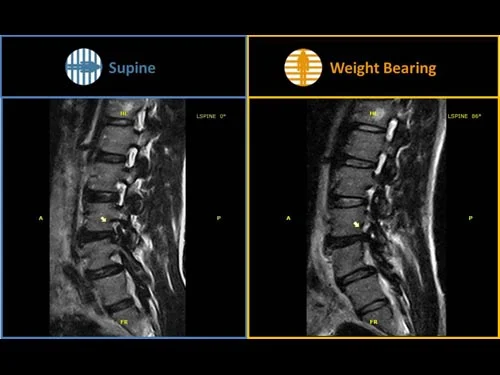

전방전위증 환자의 누워서 찍은 MRI와 서서 찍은 MRI 사진입니다.

확실히 전방전위된 정도의 차이가 더 크지요? 디스크의 형태도 함께 확인이 가능합니다.